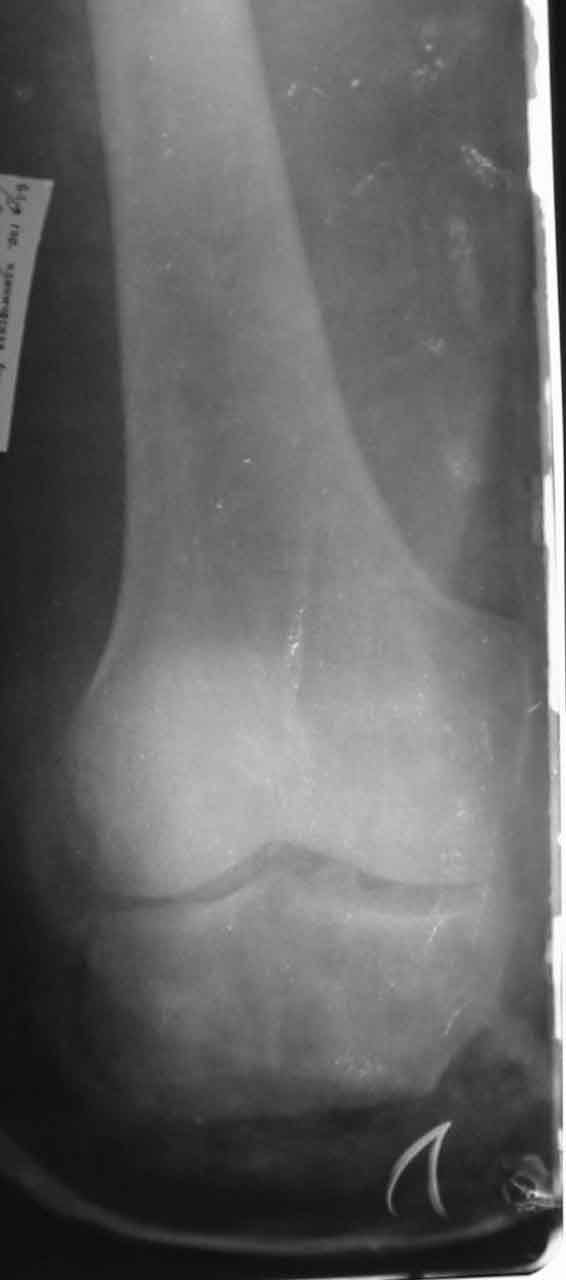

Больной С., 50 лет, строитель, поступил в 64 ГКБ 17.05.02., доставлен СП.Травма за 1 час до поступления на работе на ноги пострадавшего наехал трактор. При поступлении больного тяжелое, сознание спутаное, больной возбужден, не критичен. Кровотечения нет. Кожные покровы бледные. Пульсация на периферических артериях слабо определяется. АД 80/60 мм рт ст. Справа закрытый перелом большельшеберцовой без смещения.На Р-граммах левой голени многооскольчавый перелом костей с/3 в/3 голени (см 1)). Другие сегменты не пострадали.ДЗ. Открытый Многооскольчатый раздробленный перелом костей левой голени. Разможжениемягких тканей левой голени. Закрытый перелом с/3 большеберцовой кости правой голени со смещением. Вывих головки малоберцовой кости. Травматический шок 2-3 ст. Минуя приемное отделение больной поднят в экстренную операционную. После выведения больного из шока выполнена ПХО, и учитывая разможжение мягких тканей левой голени и многооскольчатый характер перелома - ампутация левой голени на границе в/3, экзартикуляция м/берцовой. Решено было максимально сохранить длину конечности. Ранане ушивалась, наложены провизорные швы (см 2, 3).На правую голень фиксирована разрезной гипсовой повязкой.Производились перевязки Н2 О2 , повязки с левомеколем, по мере спадения отека дозировано подтягивались провизорные швы. По состоянию на 24.05.02 Состояние больного удовлетворительное, субфибрильная лихорадка.Местно: в рану выстоят опил б/берцовой кости, кожный лоскут "болеет", некроз мышц иподкожной клетчатки в наружном углу раны (см 4).Вопросы:-Оправдана ли сберегательная тактика при поступлении?-В последующем имеет ли смысл постараться сберечь максимально возможную длинусегмента? -Если да то как заместить дефект тканей?-Если нет то какой вид ампутации выбрать и на каком уровне?Глеб КоробушкинАспирант Кафедры травматологии и ортопедии РГМУ, Москва